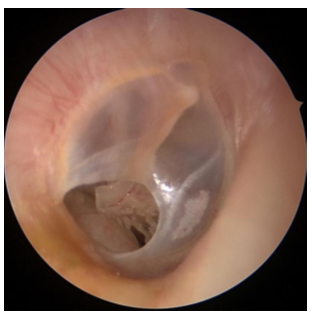

Cholesteatoma

Cyst of sqamous eputhelium usually in the ME or mastoid

Acquired cholesteatoma

Formed by retraction of TM and skin